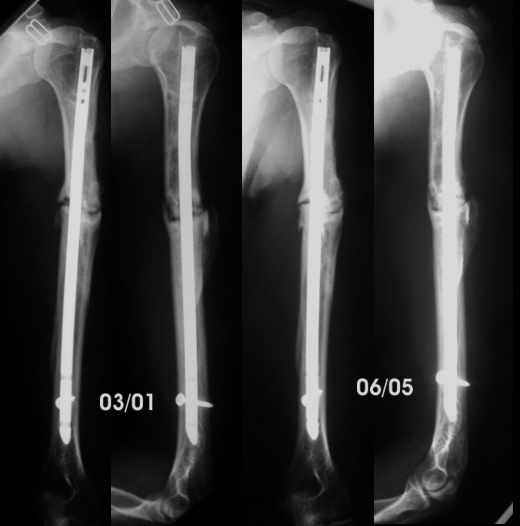

The patient regained full motion and used the arm almost freely till now. She has been working as waitress, postman... although the x-ray never showed healing. She has never wanted to be operated again because the limb was almost pain free.

She come again to my office about 2 months ago complaining of pain, she was carrying an X-ray in which it was visible that the nail was broken.Mysteriously those x-rays are lost, and in a new x-Ray I token, I couldn't see the fracture in the nail.